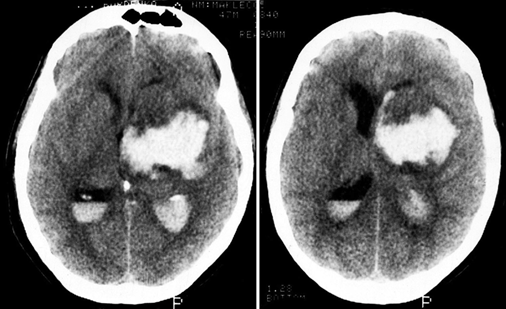

image

img95

Рис. 12.5. Внутримозговая гематома необычной формы при разрыве артериовенозной мальформации колена мозолистого тела: а — при компьютерной томографии видна гематома в проекции передних отделов мозолистого тела и глубинных отделов лобной доли, охватывающая передний рог бокового желудочка; б — при ангиографии (боковая проекция) заполняется небольшая артериовенозная мальформация в проекции колена мозолистого тела (указана стрелкой)